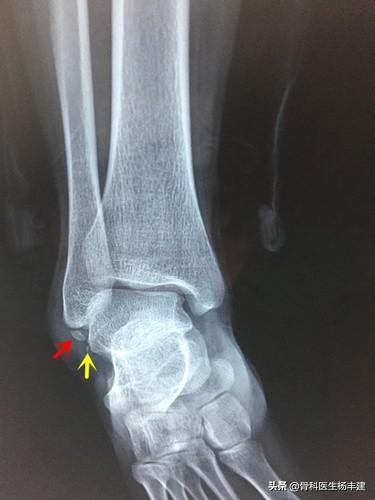

①撕脱骨折。所谓撕脱骨折,是指在踝关节扭伤时,比较大的外力作用,导致韧带与骨头相结合的位置产生比较大的撕扯力量,韧带与骨折附着处撕裂,并带了小片的骨质下来。这种损伤虽然称为骨折,但是其本质更类似于韧带损伤。这种情况多数情况下是不需要做手术的,通过石膏固定6周左右,然后进行功能锻炼,尽快恢复踝关节的灵活性即可。(需要说明,少数病人因为韧带撕裂太严重,会导致后期出现关节不稳的情况,需要做韧带重建手术。)

红色箭头以及黄色箭头处均为撕脱骨折,尤其是黄箭处的骨片极小,容易漏诊